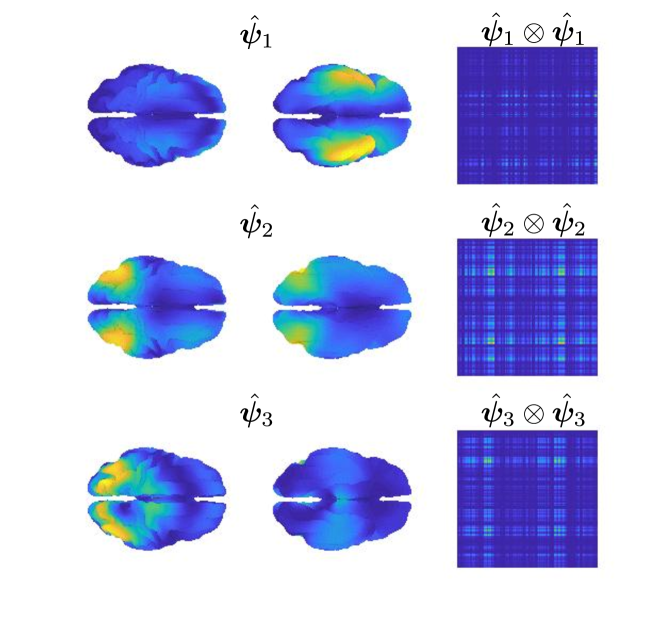

A regularization parameter common to all the PC components is chosen by inspecting the plot of the regularity of the first PC covariance functions () versus the residual norm, for different choices of the parameter. This is a version of the L-curve plot (Hansen, 2000) and is shown on the left panel of Figure B.2. Here we show the results for , in the appendices we show the results for . The energy maps of the estimated , and resulting from the analysis are shown in Figure 11. These are associated with the first three PC covariance functions , and . High intensity areas, in yellow, indicate which areas present high average interconnectivity, either by means of positive or negative correlation in time.

The second part of the analysis focuses on applying the proposed methodology to a multi-subject setting. Specifically, different subjects are considered. For each subject, the 6 minutes scan is used to compute a covariance matrix, resulting in covariance matrices . The template geometry in Figure 10 is used as a model of the brain space. Algorithm 2 is then applied to find the PC covariance functions on the template brain, associated with . We run the algorithm for iterations, and choose the regularizing parameter to be by inspecting the L-curve plot in the right panel of Figure B.2. The results for are shown in the appendices. The energy maps of the estimated functions , and and the associated first three covariance functions , and , are shown in Figure 13. High intensity areas, in yellow, indicate which areas present high average connectivity. In Figure 14, we show the subject-specific associated variances, both in the sensors space and the brain space.

The presented methodology opens up the possibility to understand population level variation in functional connectivity, and indeed, whether, just as we need different forward operators for individuals (due to anatomical differences), we should also be considering both population and subject-specific connectivity maps when analyzing connectivity networks. In fact, it is of interest to note that in both the single and multi-subject settings, the areas with high interconnectivity, displayed in yellow in Figure 11 and 13, seem to be at least partially overlapping with the brain’s default network (Buckner et al., 2008; Yeo et al., 2011). The brain’s default network consists of the brain regions known to have highly correlated hemodynamic activity (i.e. highest functional connectivity levels), and to be most active, when the subject is not performing any specific task. An image of the spatial configuration of the default network can be found, for instance, in Figure 2 of Buckner et al. (2008). From the plots of the associated variances in the sensors space (left panel of Figure 12 and Figure 14) we can see that these areas are also the ones that show high variability in connectivity across time or across subjects. This might suggest that the brain’s default network is also the brain region that shows among the highest levels of spontaneous variability in connectivity.